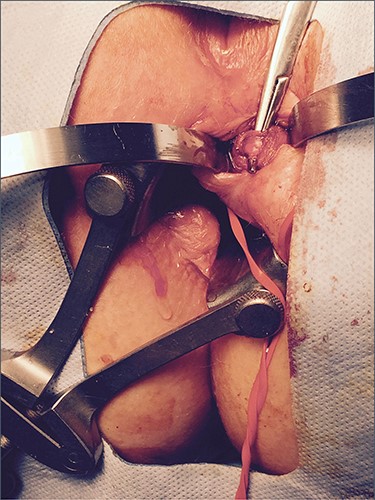

A 42-year-old female was referred for the investigation of anal pain for which 4 weeks earlier she had undergone an incision and drainage of a perianal abscess at a teaching hospital. Pus for culture (but no tissue sample) was taken. On examination, there was an external opening evident in the 4 o’clock position about 2 cm from the anal verge. In the light of an altered bowel habit, she underwent colonoscopy with no additional findings. EUA confirmed a trans-sphincteric fistula involving the lower one-third of the external anal sphincter. The distal part of the tract was partially excised for histology and a loose seton inserted. Histopathology showed a sinus tract lined by inflammatory granulation tissue but which was infiltrated by sheets of lymphocytes and plasma cells with clusters of medium and large lymphocytes, centroblasts and immunoblasts. The cells showed no viral cytopathic effects. Adjacent mature fibrous tissue showed patchy mixed inflammatory cell infiltration (Figs 1 and 2). Immunohistochemical staining confirmed a diffuse large B cell lymphoma showing CD20, BCL6 and CD10 positivity but which was BCL-2 and MUM-1 negative. There was high (>90%) Ki67 staining and slides were EBV-negative (Fig. 3). Monoclonal IGH and IGK gene rearrangements were detected consistent with a diagnosis of B cell clonality. HIV status was negative.

Histology: low-power view showing squamous mucosa (upper left) within an underlying fistula tract associated with a dense cellular infiltrate.